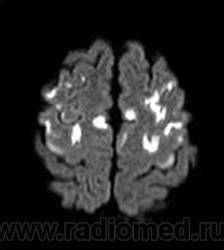

ГМ. Маркиафавы-Биньями болезнь. +

Маркиафавы-Биньями болезнь

Marchiafava, 1897, Bignami, 1903 – редко встречающийся вариант алкогольной энцефалопатии с патологистологичнски проявляющимся поражением (некрозом) мозолистого тела, образованием полостей в ткани мозга и развитием внутренней гидроцефалией. Клинически активная фаза заболевания длится от 2 до 6 лет, завершается она формированием глубокого слабоумия. В психотической стадии болезни наблюдаются слуховые и зрительные галлюцинации, апатия, депрессия, припадки, состояния возбуждения, спутанность сознания, картины псевдопаралича, а также разнообразные неврологические симптомы (тремор рук, дизартрия, абазия, арефлексия или гиперрефлексия, ослабление зрачковых реакций, изменение формы и величины зрачков и мн.др.). Лечение симптоматическое. Синонимы: Дегенерация мозолистого тела, Прогрессирующая алкогольная деменция